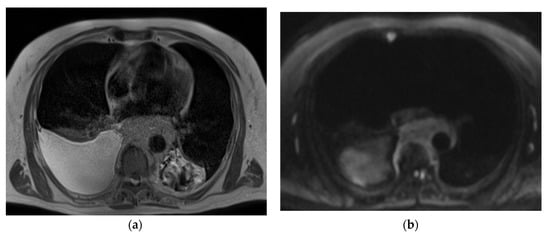

The representative T2-weighted images, DWI, and ADC maps of the malignant and benign lymph nodes are shown in Figure 2 and Figure 3 respectively.

Figure 2.

(a) T2-weighted axial MRI of a 75-year-old male shows a T2 homogeneous signal in enlarged lymph nodes encasing descending thoracic aorta; (b) Diffusion-weighted axial MRI shows diffusion restriction in most of the lymph node; (c) System generated ADC map of corresponding lymph node shows ADC mean value of 0.829 × 10−3 mm2/s. The final pathological diagnosis was lymphoma.